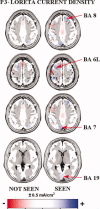

What is the timing of cortical activation related to consciousness of visuo-spatial executive functions? Electroencephalographic data (128 channels) were recorded in 13 adults. Cue stimulus briefly appeared on right or left (equal probability) monitor side for a period, inducing about 50% of recognitions. It was then masked and followed (2 s) by a central visual go stimulus. Left (right) mouse button had to be clicked after right (left) cue stimulus. This "inverted" response indexed executive processes. Afterward, subjects said "seen" if they had detected the cue stimulus or "not seen" when it was missed. Sources of event-related potentials (ERPs) were estimated by LORETA software. The inverted responses were about 95% in seen trials and about 60% in not seen trials. Cue stimulus evoked frontal-parietooccipital potentials, having the same peak latencies in the seen and not seen data. Maximal difference in amplitude of the seen and not seen ERPs was detected at about +300-ms post-stimulus (P3). P3 sources were higher in amplitude in the seen than not seen trials in dorsolateral prefrontal, premotor and parietooccipital areas. This was true in dorsolateral prefrontal and premotor cortex even when percentage of the inverted responses and reaction time were paired in the seen and not seen trials. These results suggest that, in normal subjects, the primary consciousness enhances the efficacy of visuo-spatial executive processes and is sub-served by a late (100- to 400-ms post-stimulus) enhancement of the neural synchronization in frontal areas.